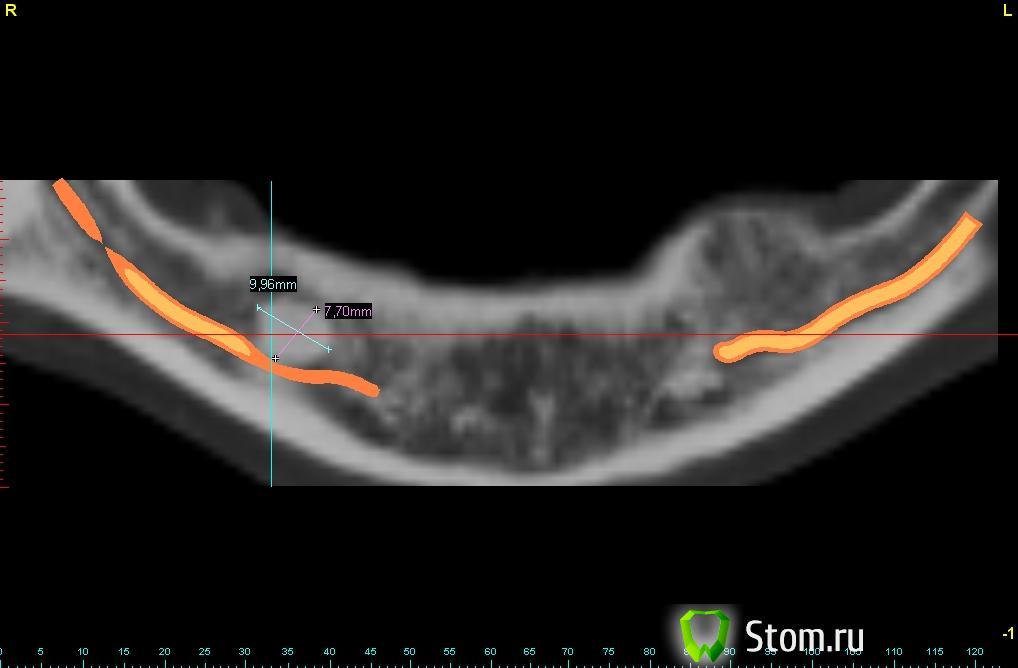

bullbull Опубликовано 16 января, 2012 Поделиться Опубликовано 16 января, 2012 (изменено) Пациентка Г. 35 лет. Обратилась в клинику для протезирования. В результате обследования обнаружено образование в области удаленного 46 зуба. Клинически данное образование никак себя не проявляет. Можно ли предложить подобный способ протезирования (на ОПГ), если пациентка откажется от радикального лечения в условиях стационара?P.S. На ОПГ полуторогодовалой давности размер образования не изменился. Изменено 16 января, 2012 пользователем bullbull Ссылка на комментарий

ПалСаныч Опубликовано 16 января, 2012 Поделиться Опубликовано 16 января, 2012 С позволения коллег выложу свое мнение:1. эта остеома не нуждается в радикальном лечении при отсутствии симптоматики2. противопоказаний для импланта нет3. 2 имплантата мне кажется маловато для такого промежутка4. Гребень в области остеомы узковат. Я бы сначала поставил блок Имхо Ссылка на комментарий

bullbull Опубликовано 16 января, 2012 Автор Поделиться Опубликовано 16 января, 2012 Планируем 3 или 4 импланта. Сомнения в том, что не "разбудим" ли мы эту штуковину?Наиболее вероятно - остеома, но нет четких контуров. А это более характерно для участков внутрикостного склероза.Может стоит перед лечением взять биопсию? Ссылка на комментарий